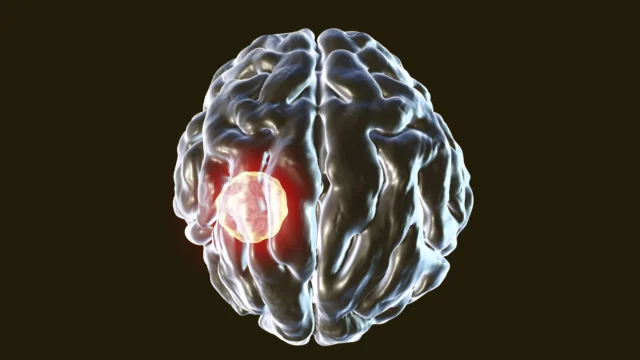

Um parasita que já pode estar vivendo em seu cérebro tem a capacidade de infectar as próprias células do sistema imunológico projetadas para eliminá-lo. Uma nova pesquisa da UVA Health explica como o corpo ainda consegue manter esta infecção sob controle.

Toxoplasma gondii é um parasita potencialmente perigoso que infecta animais de sangue quente. As pessoas são mais frequentemente infectadas pelo contato com gatos, frutas ou vegetais contaminados ou carne mal cozida. Depois de entrar no corpo, o parasita pode se espalhar por vários órgãos e eventualmente se instalar no cérebro, onde pode permanecer por toda a vida. Acredita-se que cerca de um terço da população mundial seja portadora do Toxoplasma, mas a maioria das pessoas nunca desenvolve sintomas. Quando ocorre uma doença conhecida como toxoplasmose, ela é mais grave em pessoas com sistema imunológico enfraquecido.

Pesquisadores liderados por Taji Harris, Ph.D., decidiram entender como o sistema imunológico responde quando toxoplasmose captura células T CD8+, que são células imunológicas especializadas responsáveis por matar células infectadas.

“Sabemos que as células T são muito importantes para combater Toxoplasma gondiie pensamos que sabíamos todos os motivos. As células T podem matar células infectadas ou dizer a outras células para matarem o parasita. Descobrimos que essas mesmas células T podem ser infectadas e, quando isso acontece, podem decidir morrer. toxoplasmose os parasitas precisam viver dentro das células, então a morte da célula hospedeira acabou para o parasita”, disse Harris, diretor do Centro de Imunologia do Cérebro e Glia (BIG Center) da Escola de Medicina da Universidade da Virgínia. “Entender como o sistema imunológico luta toxoplasmose importante por vários motivos. Pessoas com sistema imunológico comprometido são vulneráveis a esta infecção, e agora temos uma melhor compreensão de por que e como podemos ajudar os pacientes a combater esta infecção”.

Harris e sua equipe descobriram que as células T CD8+ dependem de uma poderosa enzima chamada caspase-8 para controlar T. gondii. A caspase-8 desempenha um papel central na regulação das respostas imunológicas e pode desencadear um processo que causa a autodestruição da célula.

Em experimentos de laboratório, camundongos cujas células T não possuíam caspase-8 apresentaram níveis significativamente mais elevados de caspase-8 T. gondii em seus cérebros em comparação com ratos cujas células T produziram a enzima. Isto aconteceu apesar de ambos os grupos terem desenvolvido uma forte resposta imunitária contra a infecção.

A diferença nos resultados foi impressionante. Os ratos com caspase-8 permaneceram saudáveis, enquanto aqueles sem ela ficaram gravemente doentes e morreram. O exame do tecido cerebral mostrou que as células T CD8+ tinham muito mais probabilidade de serem infectadas pelo parasita.

Estes resultados indicam que a caspase-8 desempenha um papel crítico na restrição T. gondii dentro das células T. As descobertas também contribuem para o conjunto de evidências de que esta enzima é essencial para ajudar o corpo a combater ameaças infecciosas.

“Examinamos a literatura científica para encontrar exemplos de patógenos que infectam células T. Encontramos muito poucos exemplos”, disse Harris, do departamento de neurociências da UVA. “Agora achamos que sabemos por quê. A caspase-8 leva à morte das células T. Os únicos patógenos que podem viver nas células T CD8+ desenvolveram maneiras de interromper a função da caspase-8. Antes de iniciar nossa pesquisa, não tínhamos ideia de que a caspase-8 era tão importante na proteção do cérebro contra toxoplasmose.”